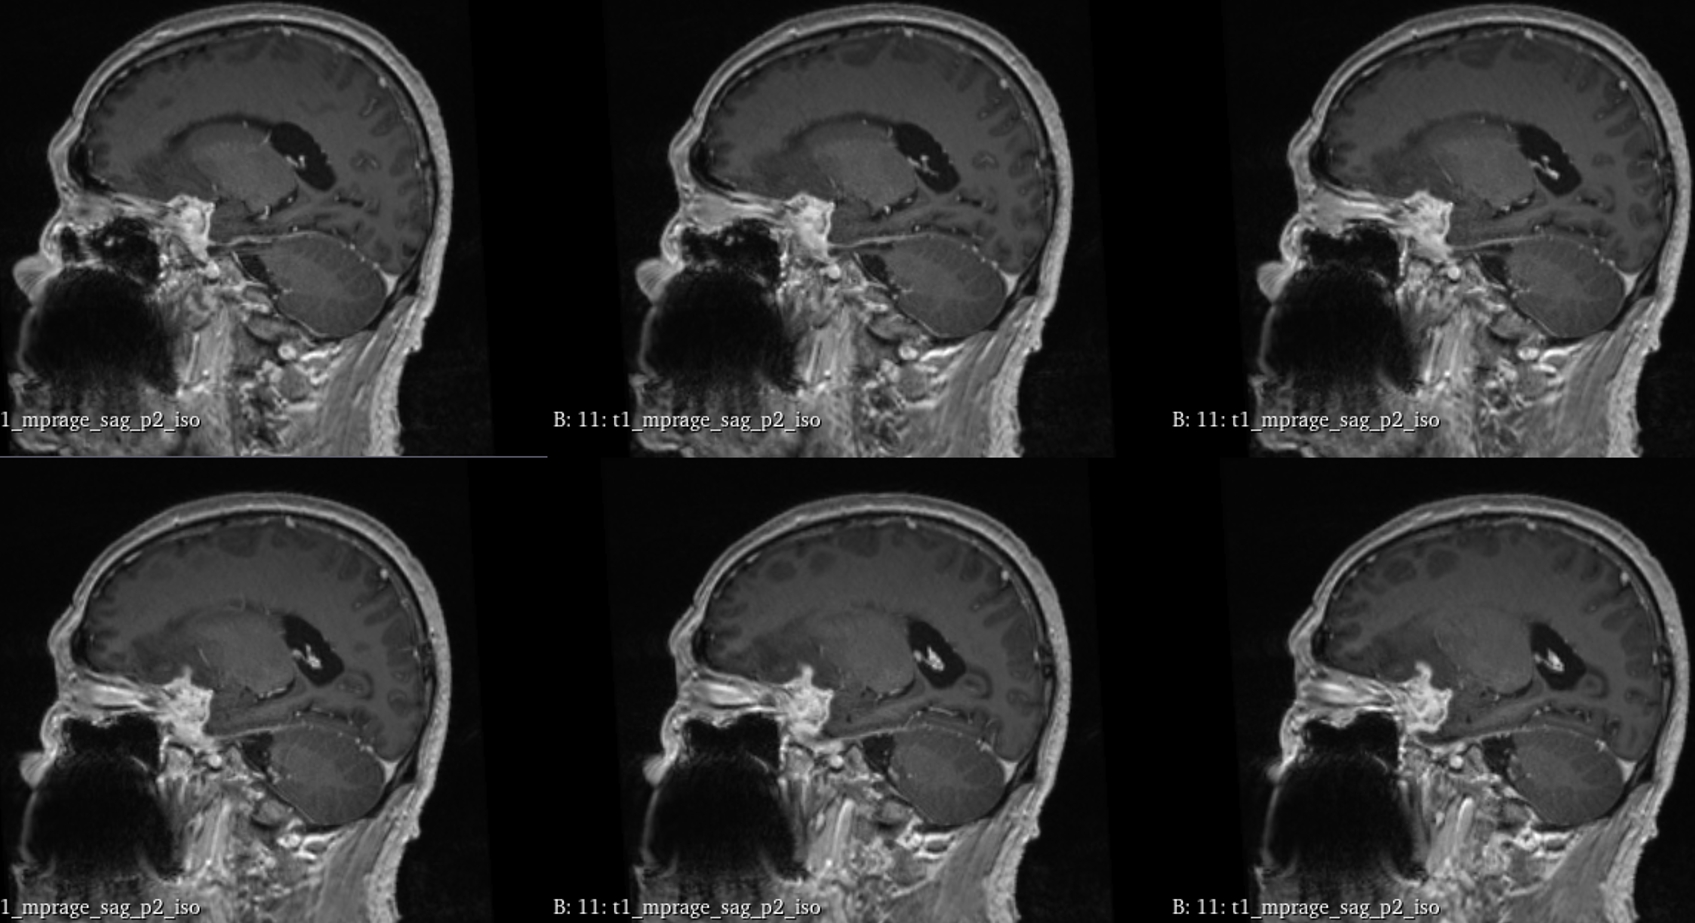

该患者入院后完善常规颅脑影像学检查,左侧颞叶病变,疾病性质不详,转移瘤、胶质瘤、炎症类疾病均不能排除,遂行PET-CT检查,提示左侧颞叶高代谢,淋巴瘤不能排除。组织MDT会诊建议可先行腰椎穿刺查脑脊液脱落细胞学、感染指标,若仍不能确诊,可进一步行开颅病灶切除,术中快速冰冻,根据冰冻结果决定手术手术策略。患者脑脊液脱落细胞学结果:较多淋巴细胞,少许单核细胞及个别中性粒细胞,未见异形细胞,脑脊液常规、生化、脑脊液培养未见细菌生长,诊断仍不能明确,且患者病情进展迅速,患者神志呈昏睡状态,颅脑MRI提示病变较前明显增大(影像学检查间隔两周),且水肿明显加重,遂行开颅病变切除术。术中见部分病变累及蝶骨嵴硬膜,病变质地硬韧,内有多个囊腔,囊内容物为黄色粘稠样脓性物质,留取囊液及实性部分送快速冰冻,在等待冰冻过程中,进一步探查见肿瘤侵犯左侧颞叶,该部位肿瘤质地相对软,无包膜,与周围脑组织无边界,血运不丰富,内有多个囊腔,且肿瘤侵犯侧裂池、颈动脉池,左侧视神经、颈内动脉、大脑中动脉均被病变包绕,且该处肿瘤质地偏硬韧。术中快速冰冻提示组织大片变性坏死,伴胶质增生及淋巴增生。结合病变质地及冰冻结果,考虑为非肿瘤性疾病,可能为炎性病变伴肉芽肿形成可能性大,且肿瘤质地硬韧,累及范围广泛,难以全切,遂行肿瘤大部分切除后结束手术。术后病理结果明确后予以伏立康唑、醋酸卡泊芬净抗真菌治疗。在治疗过程中患者先后出现脑出血、脑梗塞,最终因治疗周期长,花费高、效果不确定等因素,家属放弃治疗,于术后1月去世。

颅内曲霉菌病(intracranial aspergillosis,ICA),又称中枢神经系统曲霉菌病,是一种由曲霉菌侵袭感染脑实质、脑膜(硬脑膜为主)、脑血管及海绵窦等颅底结构引起的侵袭性真菌病。ICA由Oppe首次报道于1897年,该病临床少见,但随着激素、免疫抑制剂及广谱抗生素的广泛应用,其发病率逐年上升。ICA的临床及影像学表现缺乏特异性,核心症状异质性大,诊断及鉴别诊断困难。ICA占颅内真菌感染的5%-10%,占侵袭性曲霉菌感染的14%-42%,ICA更易累及男性,男女比例为2.25∶1。曲霉菌在自然界中广泛存在,是一种机会致病菌。其分生孢子可经呼吸道进入人体,定植于肺部、鼻窦等空腔内。当机体免疫力降低时,曲霉菌在组织、器官或血液中生长、繁殖,导致炎性反应及组织损伤,可经两种途径即局部浸润及血行播散侵入颅内导致ICA。据报道,18.0%-66.7%的患者由鼻窦、中耳及乳突中的曲霉菌感染浸润引起(窦源性ICA),该患者合并慢性鼻窦炎,考虑为窦源性。ICA可累及脑血管、脑实质、脑膜(硬脑膜为主)及颅底结构,导致坏死、化脓及慢性肉芽肿。曲霉菌侵及脑血管后,既可因菌丝填充或炎性反应导致脑梗死,又可因曲霉菌性动脉瘤破裂导致脑出血或蛛网膜下腔出血。该病多呈急性或亚急性起病,进行性加重,临床表现多样且缺乏特异性。

GM实验,GM是曲霉菌细胞壁的主要成分,是疾病早期释放至体液中的抗原之一。据报道,脑脊液GM试验诊断ICA的敏感度及特异度分别为88.2%及96.3%,且阳性预测值及阴性预测值均超过90%,脑脊液GM水平与曲霉菌感染严重程度相关,监测该指标可评价治疗效果及预后。影像学检查具有多样性,多为反复慢性炎症、肉芽肿样改变,部分易累及颅底。

目前确诊ICA仍依赖于病灶切除或活检,获得组织病理学、直接镜检或培养证据。《颅内曲霉菌病诊治中国专家共识》推荐:当临床症状怀疑ICA时,应尽早行脑脊液检查(常规、生化、培养、G试验、GM试验及mNGS)及颅脑MRI平扫+增强检查。怀疑窦源性ICA时,还应加做颅底CT检查。当临床症状符合ICA,但上述检查结果为阴性时,可重复送检。条件允许时,及时行标本镜检与培养获得确切证据。尤其是对于长期应用激素、免疫功能缺陷高危患者。